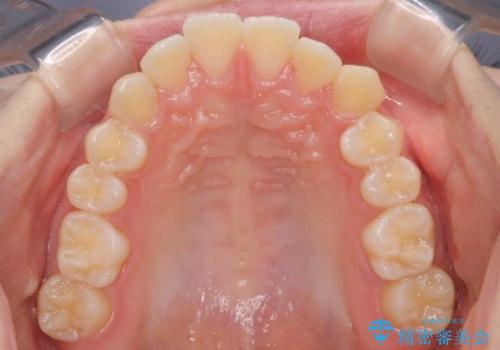

- 出っ歯を主訴に来院されました。今回は4番の歯を4本抜歯をし、ワイヤー矯正にて治療しました。

抜歯矯正のため2年を予定してましたが、予定よりも早く終わることができました。また口元も下がり、かみ合わせも改善しました。